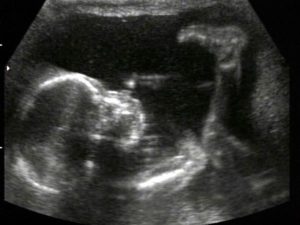

УЗИ, проведенное на 21 неделе беременности, позволяет определить пол будущего малыша, увидеть внутренние органы.

Специалист ультразвуковой диагностики оценит вероятность развития патологий, определит частоту биения сердца ребенка и состояние амниотической жидкости, установит степень двигательной активности, проведет измерения матки и плода.

При желании будущая мама сможет сама все увидеть, если УЗИ проведут в 3Д или 4Д формате, и сделать первую фотографию ребенка.

Ультразвуковое исследование на 21-й неделе беременности позволяет детально осмотреть плод, оценить его развитие, определить пол, а также проверить обвитие пуповиной, состояние плаценты, уровень околоплодных вод и матки. Кровоток в сосудах матки и плаценты анализируется с помощью допплерографии. Процедура безопасна, безболезненна и важна для специалистов.

На 21-й неделе беременности при ультразвуковом исследовании пол ребенка становится ясным. У девочек половые органы представлены двумя параллельными линиями, у мальчиков — небольшим копьевидным выступом.

На 21-й неделе беременности органы и системы плода сформированы, постепенно увеличиваются в размерах, начинают выполнять свою функцию. Головной мозг функционирует активнее – малыш улыбается, хмурится, совершает хватательные движения ручками, перебирает ножками.

Личико малыша врач осматривает особенно внимательно, поскольку на данном сроке можно диагностировать внешние дефекты: хейлосхизис и расщепление неба (в обиходе «заячья губа» и «волчья пасть»). Развитие носовых костей указывает на возможные генетические патологии хромосомного характера.